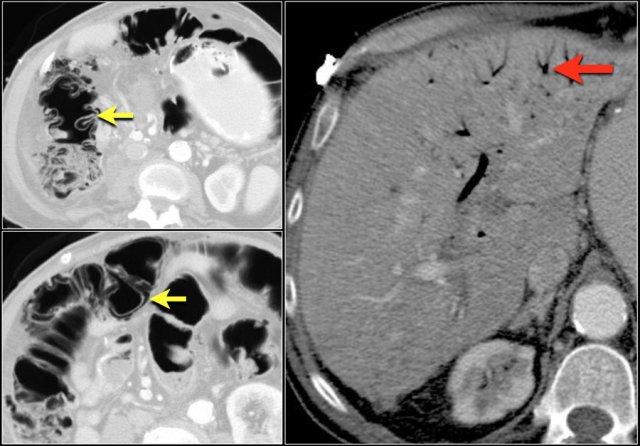

Đây là một bệnh nhân khác bị thiếu máu cục bộ một đoạn dài ruột non do tắc ruột quai kín.

Một đặc điểm hình ảnh quan trọng của tắc ruột quai kín là hình ảnh các quai ruột non giãn xếp theo kiểu nan hoa bánh xe với các mạch máu mạc treo hội tụ về một điểm trung tâm.

Các dấu hiệu thiếu máu cục bộ trong tắc ruột quai kín tương tự như ở các bệnh nhân có nguyên nhân thiếu máu cục bộ mạc treo khác:

- Dày thành ruột

- Phù nề mạc treo ruột

- Cổ trướng

- Sự ngấm thuốc của thành ruột trong thiếu máu cục bộ có thể bình thường, tăng do hiện tượng tái tưới máu, hoặc giảm/mất ngấm thuốc như trong trường hợp này.

Đôi khi, tái tạo ảnh mặt phẳng coronal dạng lát cắt dày (thick slab coronal reconstructions) có thể hữu ích trong việc đánh giá mức độ ngấm thuốc.

Điều này được minh họa rõ ràng ở bệnh nhân này, trong đó hỗng tràng ngấm thuốc tốt (vùng xanh lá), trong khi hồi tràng giảm ngấm thuốc (vùng đỏ) do thiếu máu cục bộ.

Đây là một trường hợp tắc ruột quai kín khác.

Lưu ý sự khác biệt về mức độ ngấm thuốc giữa các quai ruột bình thường không giãn (mũi tên xanh lá) và các quai ruột giãn bị thắt nghẹt (mũi tên đỏ).

Ở trung tâm là các mạch máu mạc treo bị xoắn vặn (mũi tên vàng).